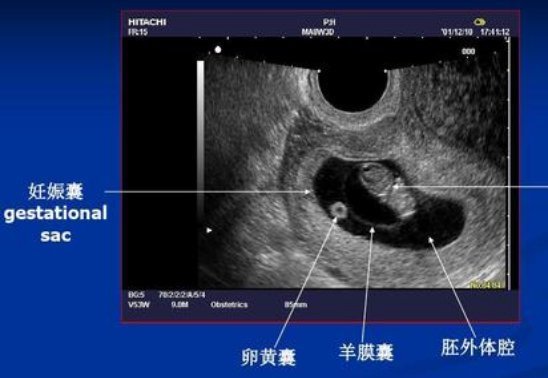

情况一:刚怀孕去做确认检查

大多孕周较小,一般在怀孕4-5周。

可能做B超也可能做阴超检查,主要看孕囊着床位置(排除宫外孕)。

但这次B超可做可不做,并非“必须查”项目,具体听医生安排就好。